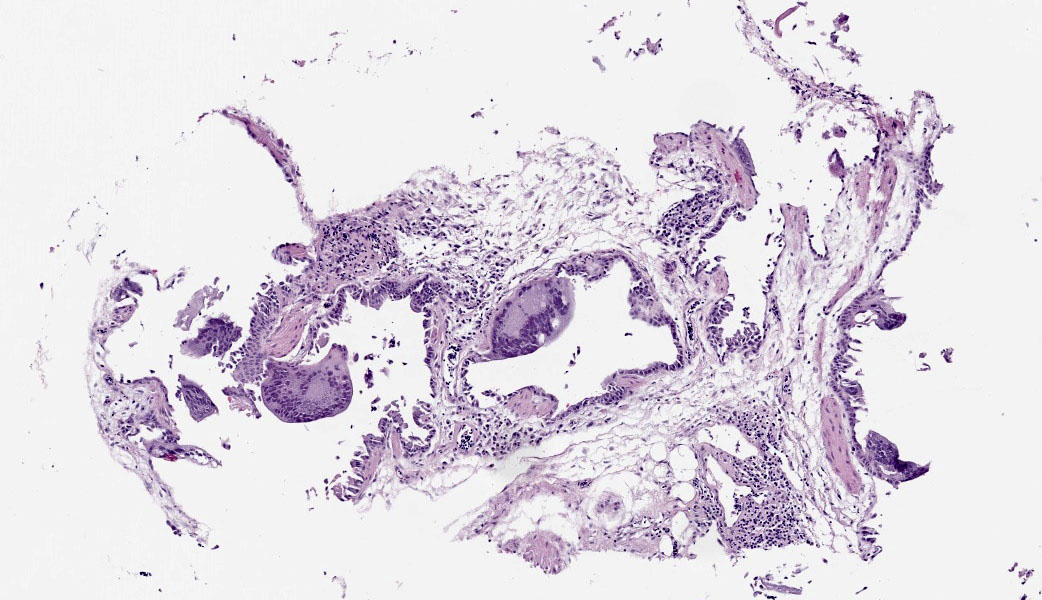

Microscopic Description:

The bronchi and parabronchi contain numerous large syncytia with large amphophilic-to-eosinophilic intranuclear inclusions that marginalize the chromatin. Bronchi and parabronchi also often contain foamy macrophages, pale basophilic mucus, homogeneously eosinophilic edema fluid, fibrin, cellular debris, and sloughed necrotic epithelial cells.

- Tubular reproductive tract, air sac, lung: Epithelial necrosis, acute, multifocal, moderate, with intranuclear viral inclusions and numerous syncytia.

The JPC’s own Dr. Elise LaDouceur moder-ated this year’s avian-focused seventeenth conference. This first case provided participants with a panoply/salmagundi/”dog’s breakfast” of tissues to sort through to achieve a diagnosis. The characteristic intranuclear viral inclusion bodies of herpesvirus were best seen in the air sac respiratory epithelium, which also rewarded conference-goers with some exceptional viral syncytia. Of the potential herpesviral culprits, psittacine al-phaherpesviruses (PsAHV) 1, 3, and 5 have been reported in psittacine species, including Indian ringneck parakeets, and PsAHV-5 was isolated by the contributor in this case. The contributor provided some beautiful electron microscopy (EM) photos from this bird that demonstrated intranuclear herpesviral virions, with some virions budding from the nuclear envelope to become enveloped themselves, and others hanging around the rough endo-plasmic reticulum (RER) to acquire additional proteins. The JPC is grateful to the contributor for providing these excellent educational images!